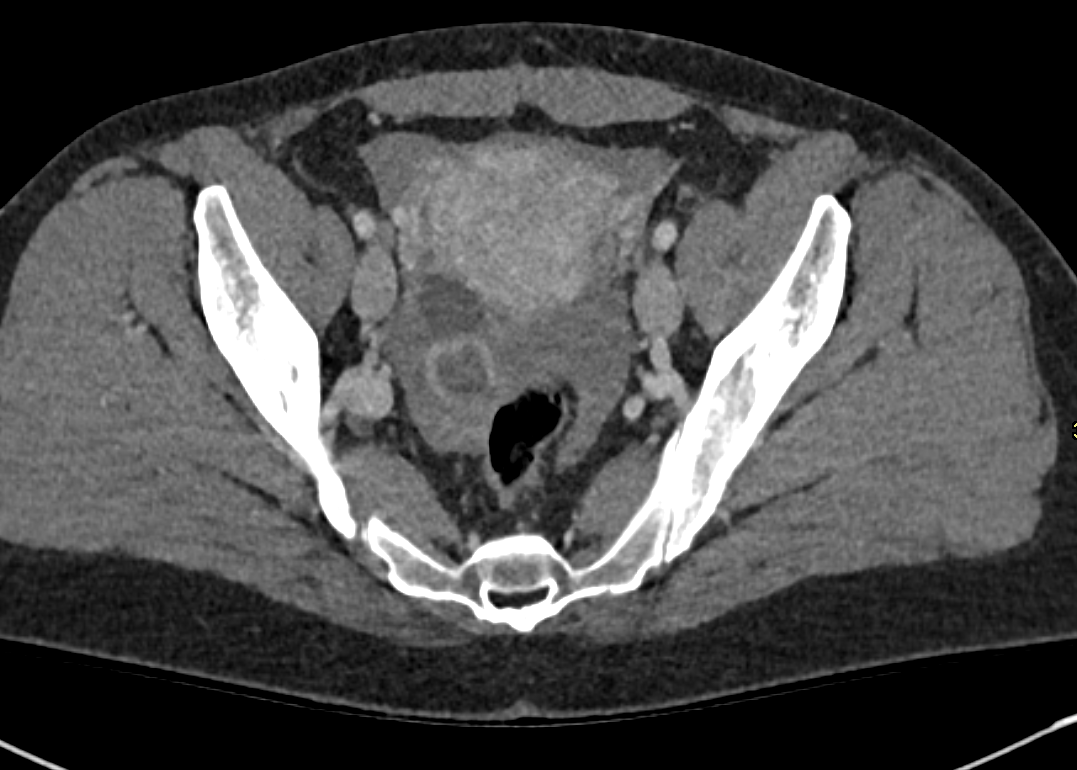

Ruptured Corpus Luteal Cyst